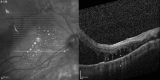

Background: To draw comparisons between spectral domain optic coherence tomography (SD-OCT) features of subretinal silicon oil (SO), perfluoro-n-octane (PFO) or C3F8 gas.

Methods: Cases diagnosed with retained subretinal vitreous substitutes (VS) were retrospectively selected. Demographic data were collected and OCT features were analyzed.

Results: In the 13 cases with subretinal PFO, hyper-reflectivity under the bubble was noted in 8 eyes (61.5%); choroidal shadow at the borders of the bubble in 11 eyes (84.6%); hyper-reflective halo around the bubble in 5 eyes (38.4%) and a hyper-reflective apical dot in 8 eyes (61.5%).The two cases with multiple PFO bubbles had complete septum dividing the bubbles. The one case with subretinal SO had hyper reflectivity under the bubble; no choroidal shadow at the edge of the bubble; hyper-reflective halo was noted around the bubble and the apical hyper-reflective dot was present; there was no complete septum dividing multiple bubbles. The single case with subretinal C3F8 had some bubbles with totally round base, incomplete septum, hyper reflectivity under the bubble, choroidal shadow at the edge of the bubble, a hyper-reflective halo and an apical dot.

Conclusion: Different subretinal VS share similar SD-OCT characteristics. Round base bubbles are only observed with subretinal C3F8 gas, while incomplete septum are related to retained subretinal SO or gas.